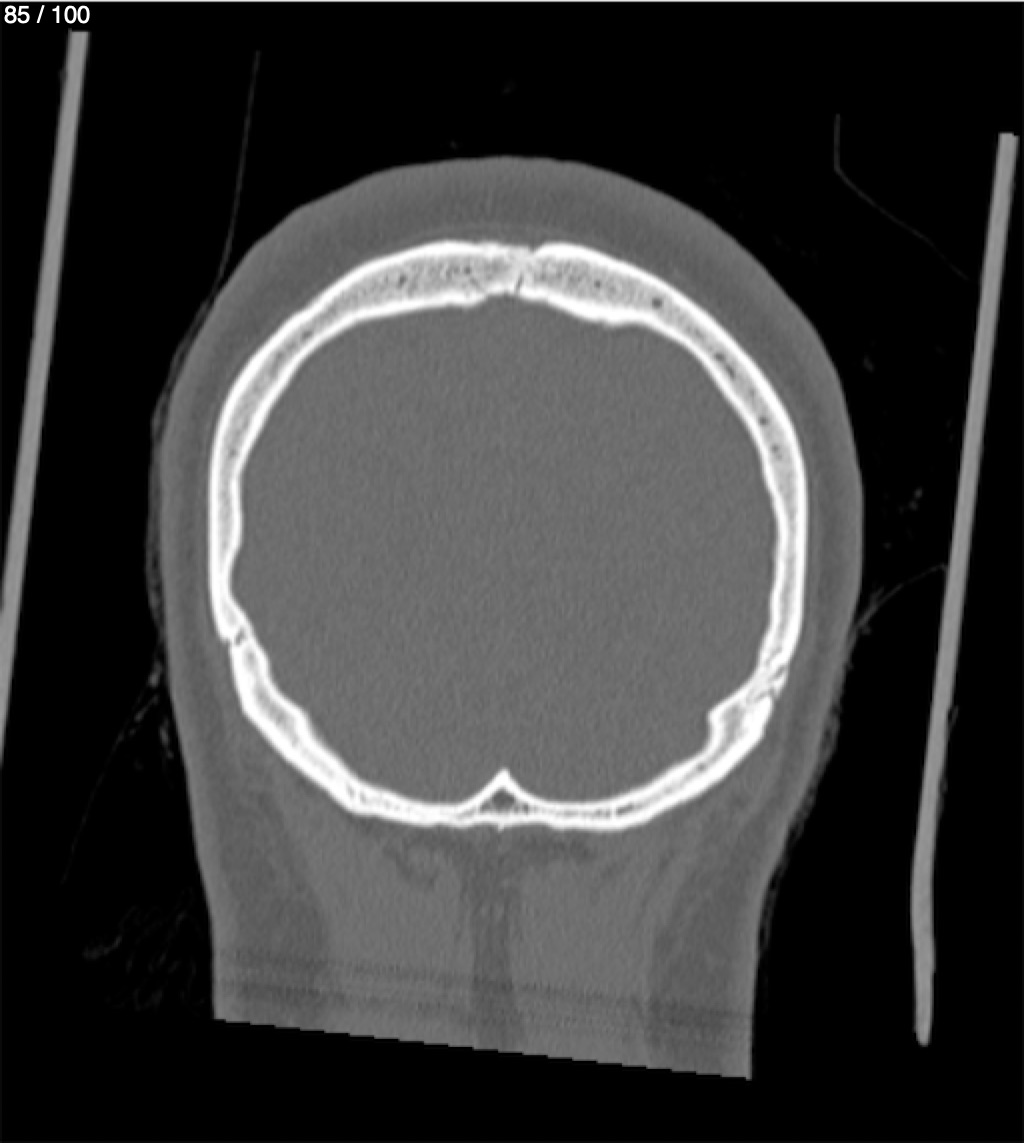

Reybet Garcia Fuentes 30A - T.C Craneo